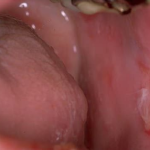

Pemphigus Mucosae = فقاع الاغشية المخاطية